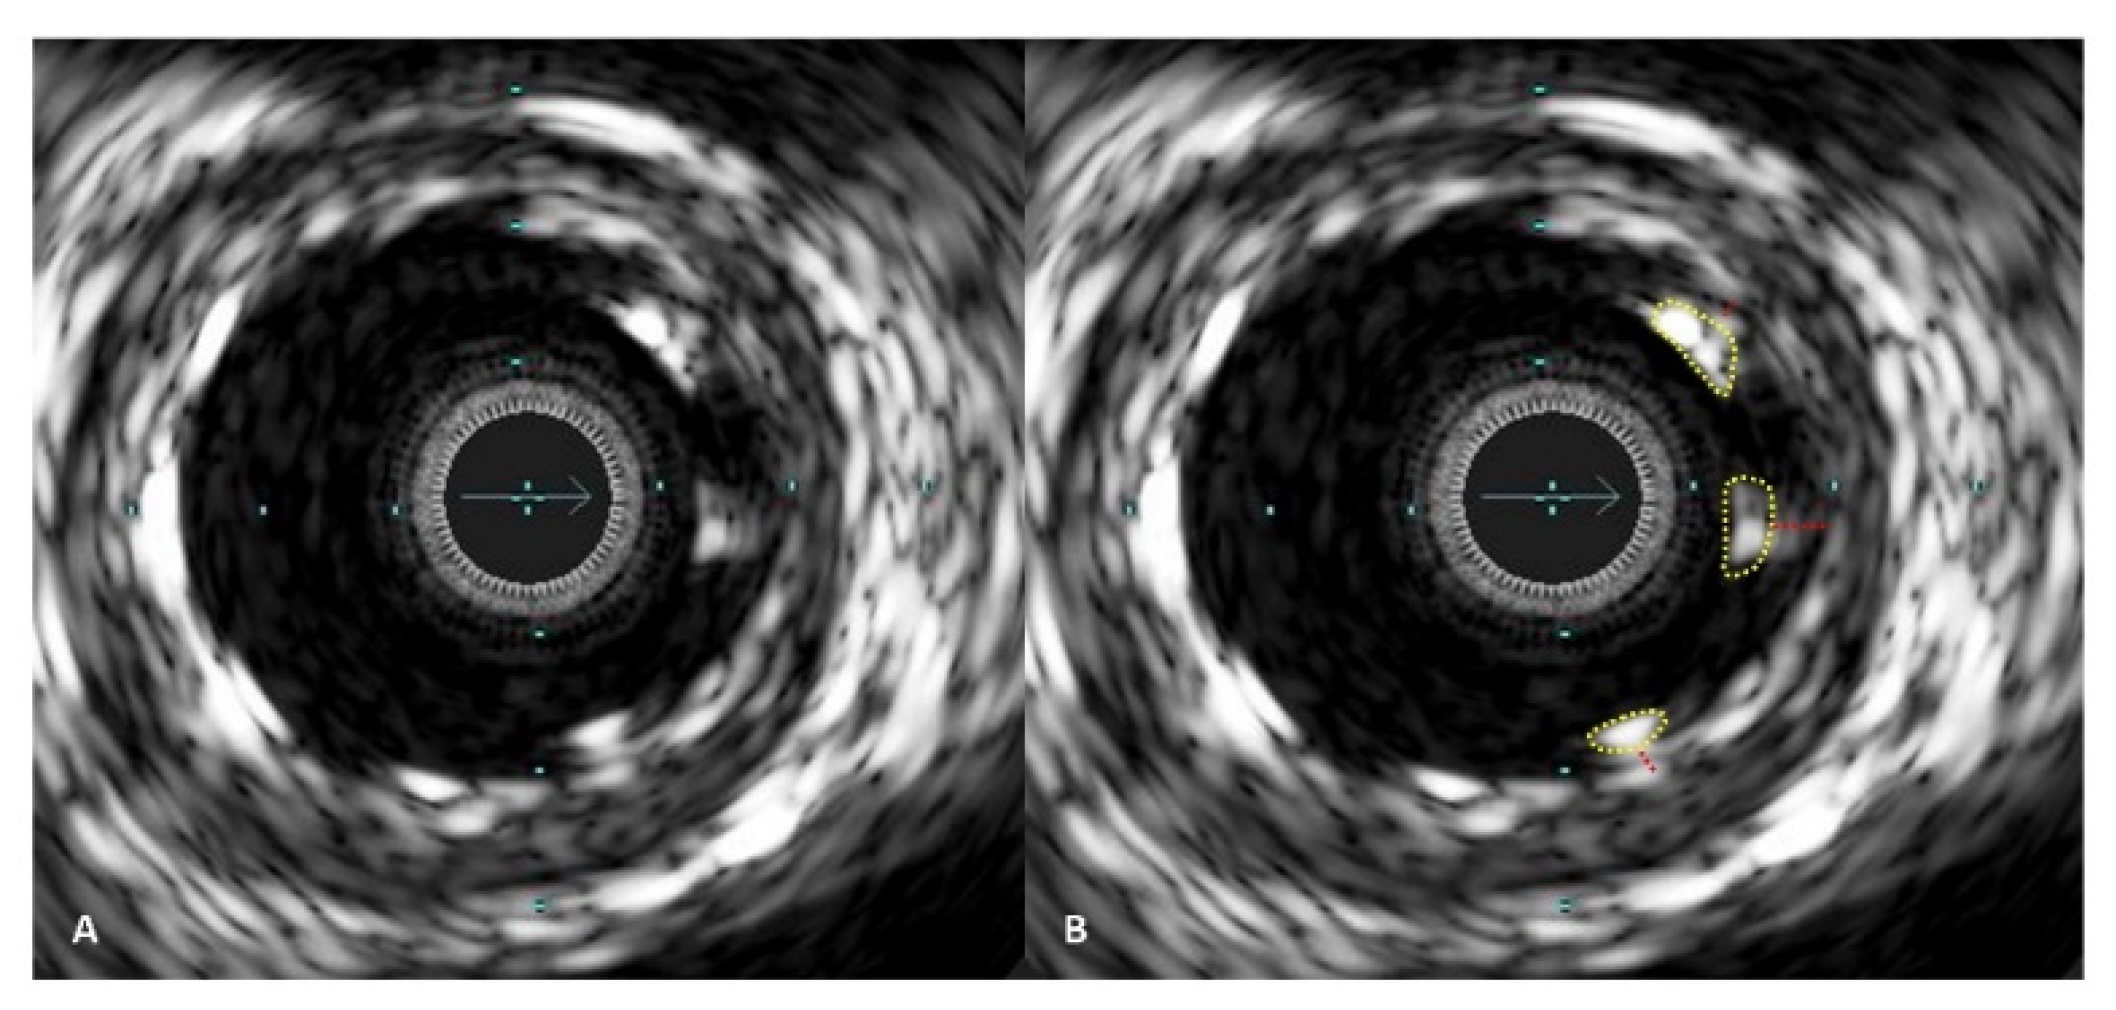

Figure 4. IVUS images demonstrating stent malapposition. In picture (A), malapposed stent struts are visible on one side of the artery. In picture (B), the malapposed stent struts are marked with a yellow line, and the red lines indicate the distance between the stent struts and the vessel wall inner layer.